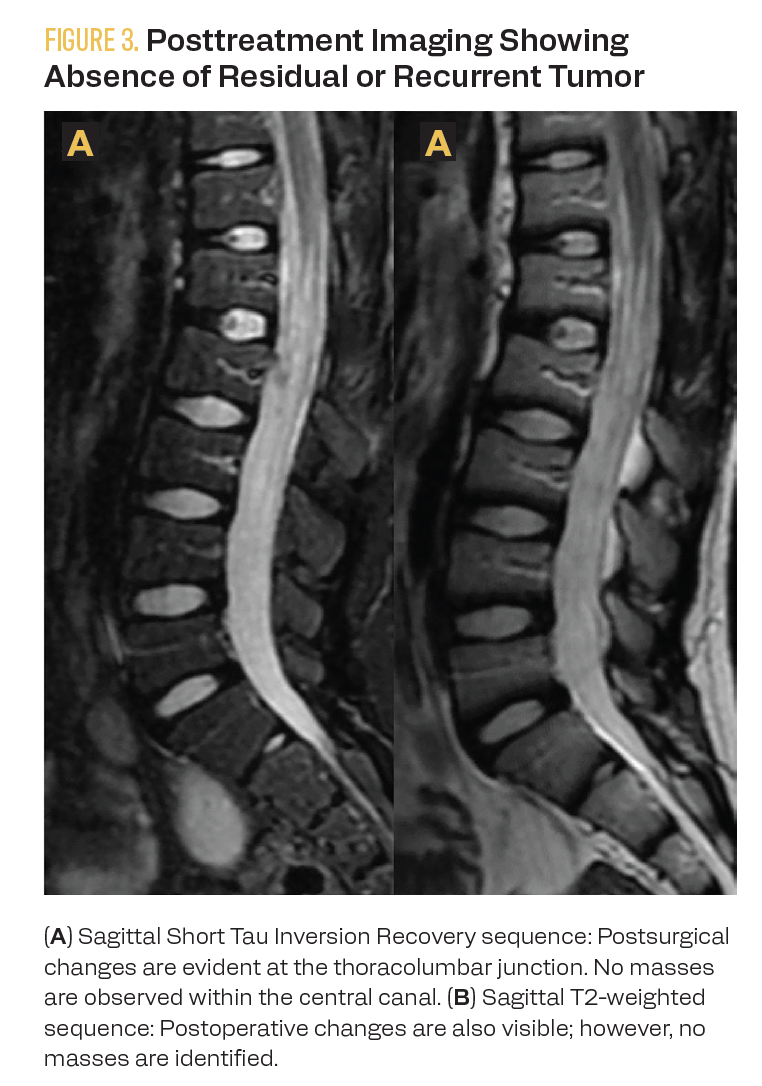

A staging PET-CT with fluorodeoxyglucose (FDG) was performed at diagnosis and for end-of-treatment evaluation. Initially, the functional imaging reported a nodal conglomerate in the pelvic region and the absence of the left kidney. However, renal scintigraphy revealed the abnormal location of the right kidney in the pelvic region, ruling out abdominal nodal tumor involvement. End-of-treatment FDG PET-CT showed no evidence of hypermetabolic lesions suggesting lymphoproliferative tumor involvement. Anatomical imaging with MRI at the end of treatment showed no evidence of tumor recurrence (Figure 3). Eighteen months after diagnosis, the patient is undergoing follow-up care, with no evidence of tumor recurrence or relapse.

FIGURE 3. Posttreatment Imaging Showing Absence of Residual or Recurrent Tumor